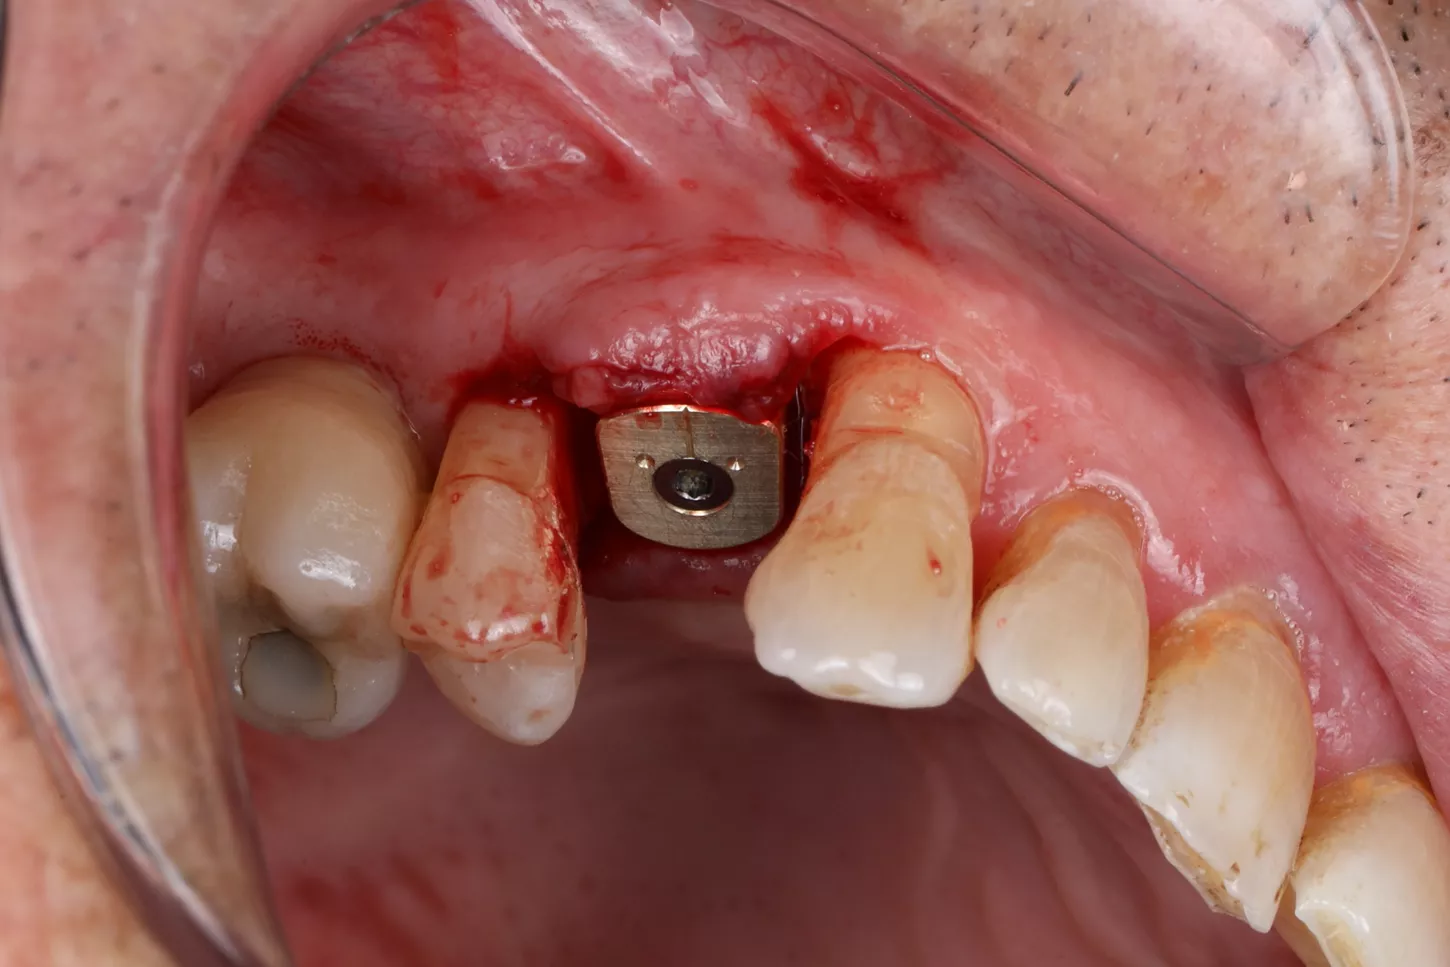

Phase III: Guide design (Fig 3a. 3b. 3c) for guided Implant Placement and Soft-Tissue Augmentation

After healing, implant placement was performed using a tooth-supported surgical guide under local anaesthesia. A limited buccal flap allowed visual control and creation of a pouch for a connective tissue graft. Osteotomy was completed with the Integral surgery kit, and a 3.4×12 mm Axiom® X3 implant (XT34120) was placed under fully guided conditions with a Healfit® SH (OPSHSC23) healing abutment connected. A palatal connective tissue graft was positioned buccally to enhance soft-tissue thickness. The flap was sutured with 5-0 interrupted and mattress sutures. Postoperative care mirrored Phase I, with uneventful healing observed (Fig 4 a&b).

4a. 4b. Lateral view showing Healfit® SH healing screw connected to the implant and occlusal view of sutures for tension-free closure.